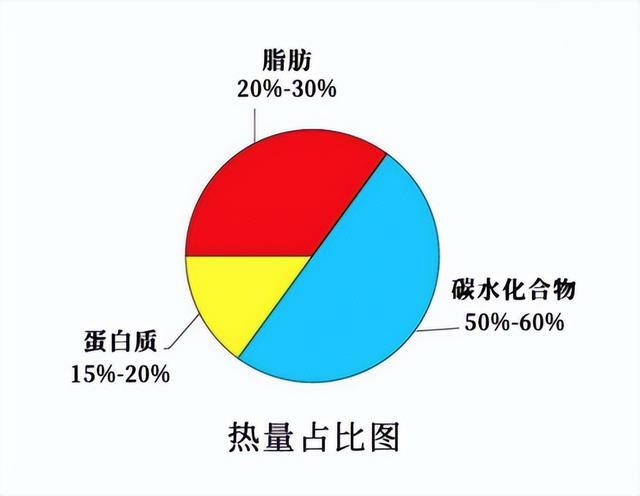

石老師介紹,碳水化合物、脂肪、蛋白質作為三大產熱(提供能量)營養素,碳水化合物和脂肪有節約蛋白質的作用,為什麼這麼說呢?在碳水化合物和脂肪為身體供能產熱之後,蛋白質才不至於全部去參與能量的生成,能更好地去發揮其他的重要作用。也就是說,如果你的碳水、脂肪攝入不夠,蛋白質會優先發揮產熱的功能。

所以,想更好地讓蛋白質發揮作用,碳水、脂肪的攝取就必須得跟得上,不能說蛋白質好,我們進食就只吃蛋白質,瘋狂補蛋白粉,而忽視了其他能量的來源(碳水化合物、脂肪)。能量攝入不足時,蛋白質會先發揮產熱作用,浪費了它原本的價值。而且,蛋白質最終的代謝產物是含氮產物,一味地補蛋白也會給肝腎代謝增加負擔。